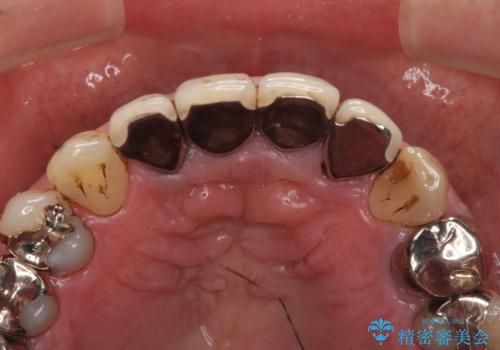

老朽化した前歯のクラウンやりかえ

- 10数年前に治療した上顎前歯のクラウンをやり替え、審美性を回復したいと希望され来院されました。

X線写真より問題のなかった根管治療は行わず、クラウンを除去し仮歯でを装着したのちジルコニアクラウンを製作していきます。